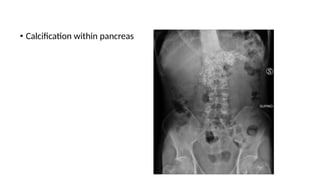

• Calcification within pancreas

-pancreatic calcification on AXR